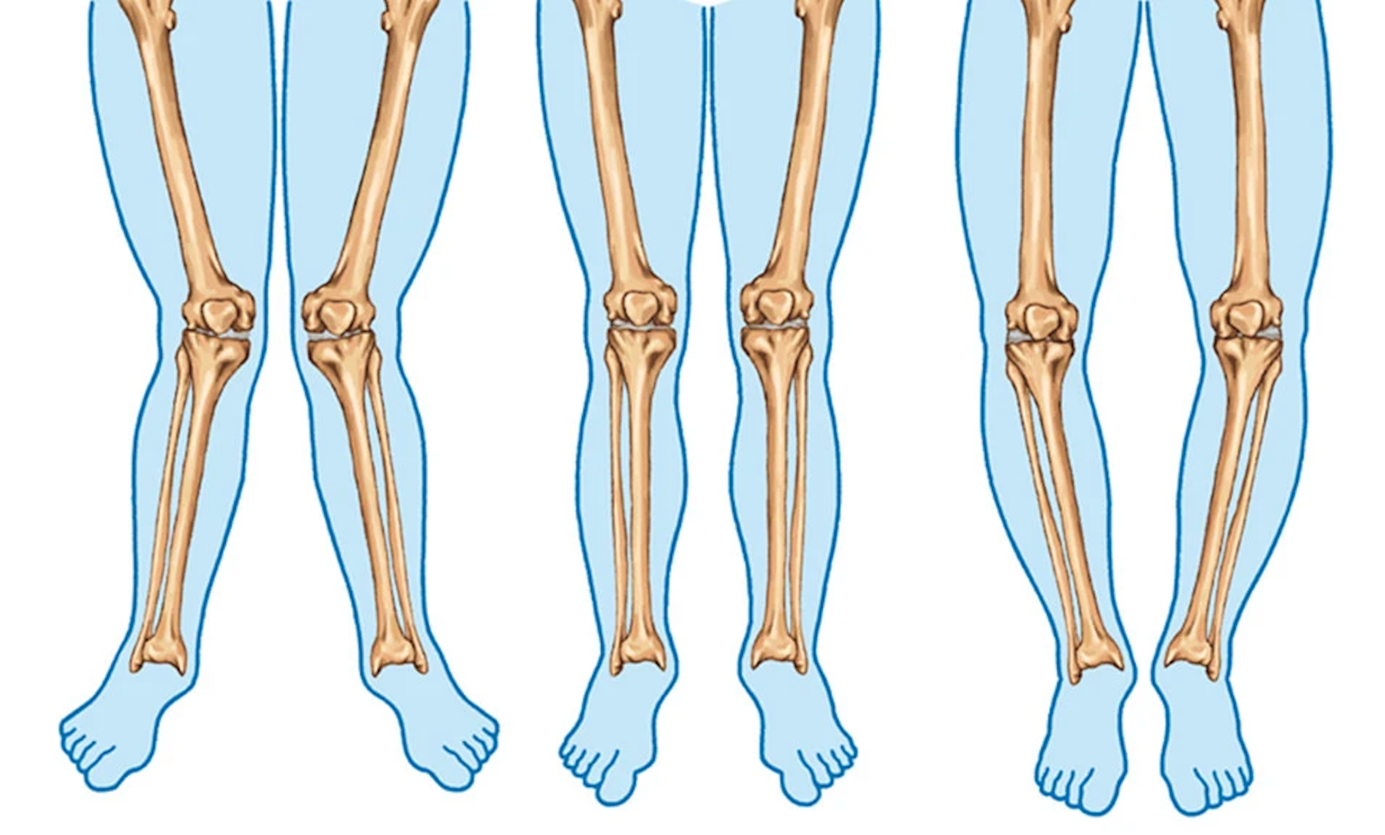

A.Varus diz görünümü

B. Yüksek tibial osteotomi kesisi

C. Kemik kama çıkarılması ve dizilimin düzeltilmesi